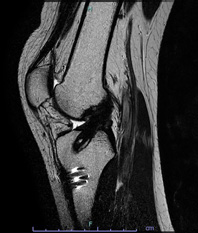

• 画像:断裂した十字靱帯(MRI)

断裂した十字靱帯(MRI)

• 画像:再建した前十字靱帯(MRI)

再建した前十字靱帯(MRI)